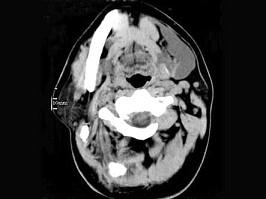

问题 男,32岁,左侧下颌部肿块,CT如图所示,最可能的诊断是 ( )

选项 A、颈部淋巴管瘤 B、舌下腺囊肿 C、颌骨囊肿 D、鳃裂囊肿 E、造釉细胞瘤

答案 B